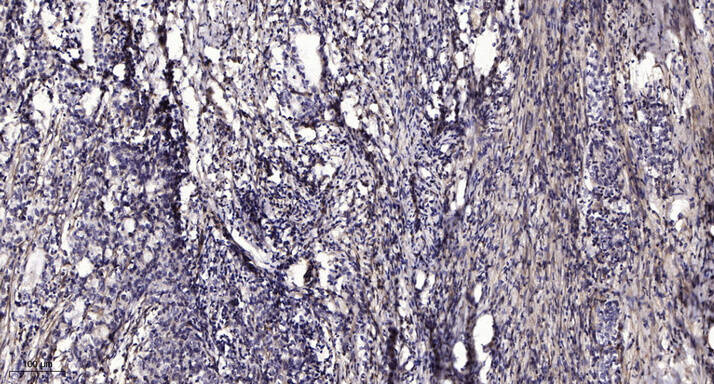

Immunohistochemical analysis of paraffin-embedded human Gastric adenocarcinoma. 1, Antibody was diluted at 1:200(4° overnight). 2, Tris-EDTA,pH9.0 was used for antigen retrieval. 3,Secondary antibody was diluted at 1:200(room temperature, 45min).